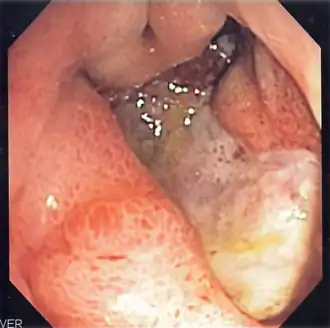

Ulcer gastric profund | |

Ulcerul gastroduodenal sau ulcerul gastric și duodenal este o boală de etiologie insuficient cunoscută care se caracterizează, din punct de vedere anatomic, prin prezența unei ulcerații cronice circumscrise care se localizează la nivelul mucoasei gastrice (ulcerul gastric) sau mucoasei duodenale (ulcerul duodenal) sau la nivelul ambelor și care se caracterizează printr-un sindrom clinic cu o evoluție cronică în pusee, în care fazele evolutive alternează cu cele de acalmie. Pentru desemnarea concomitentă a leziunii, simptomelor și a cauzei se utilizează termenul boală ulceroasă gastroduodenală sau boală ulceroasă. Ulcerul poate avea dimensiuni variind de la câțiva milimetri la câțiva centimetri. Ulcerul se deosebește de eroziune prin adâncimea penetrației; eroziunea este mai superficială și nu ajunge la musculara mucoasei. Cauza ulcerului gastroduodenal este legată de prezența unui germen microbian (Helicobacter pylori), de utilizare de AINS (antiinflamatoare nesteroidiene), de factori alimentari, stres, și mai rar de o hipersecreție de gastrină (sindromul Zollinger-Ellison).[3][4][5][6][7]

Ulcerul gastroduodenal reprezintă o leziune în mucoasa stomacală, în prima parte a intestinului subțire sau, ocazional, în partea de jos a esofagului.[9][10] Un ulcer la stomac este cunoscut drept ulcer gastric, în timp ce acela care se află în prima parte a intestinelor este cunoscut drept ulcer duodenal. Cele mai comune simptome reprezintă trezitul în noapte, acuzând dureri în partea superioară a abdomenului sau dureri în partea superioară a abdomenului ce se îmbunătățesc odată ce persoana mănâncă. Durerea este adesea descrisă ca o arsură sau durere suportabilă. Alte simptome includ eructația, starea de vomă, scăderea în greutate sau poftă de mâncare scăzută. Aproximativ o treime dintre persoanele în vârstă nu prezintă simptome.[9] Complicațiile pot include sângerări, perforare și blocajul stomacului. Sângerarea apare la aproximativ 15% dintre oameni.[11]